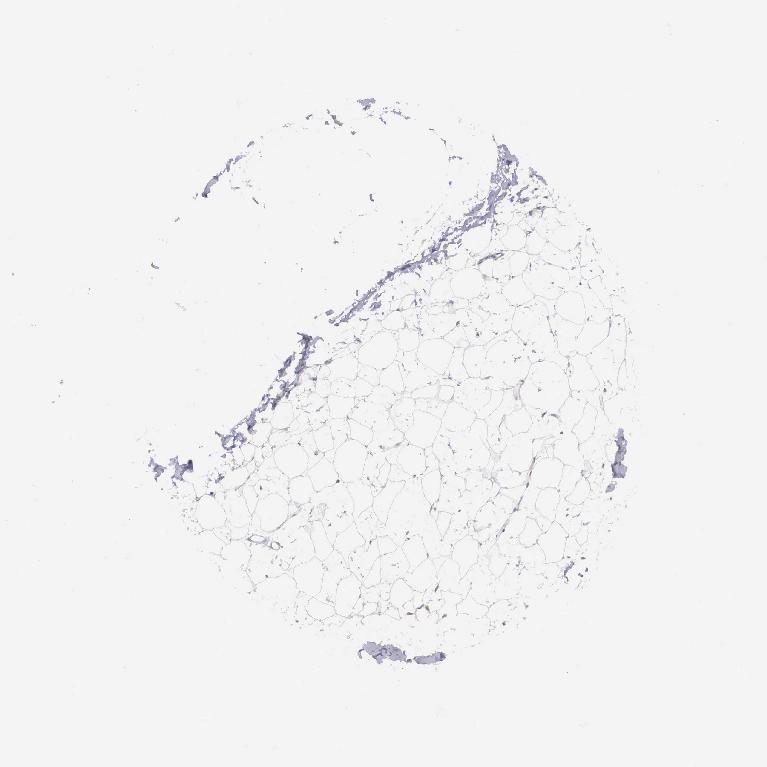

ADIPOSE TISSUE - Antibody stainingi

Antibody staining in the annotated cell types in the current human tissue is reported as not detected, low, medium, or high, based on conventional immunohistochemistry profiling in selected tissues. This score is based on the combination of the staining intensity and fraction of stained cells.

Each image is clickable and will lead to virtual microscopy that enables deeper exploration of all samples and also displays staining intensity scores, fraction scores and subcellular localization as well as patient and tissue information for each sample.

Antibody HPA000545

Adipocytes Not detected